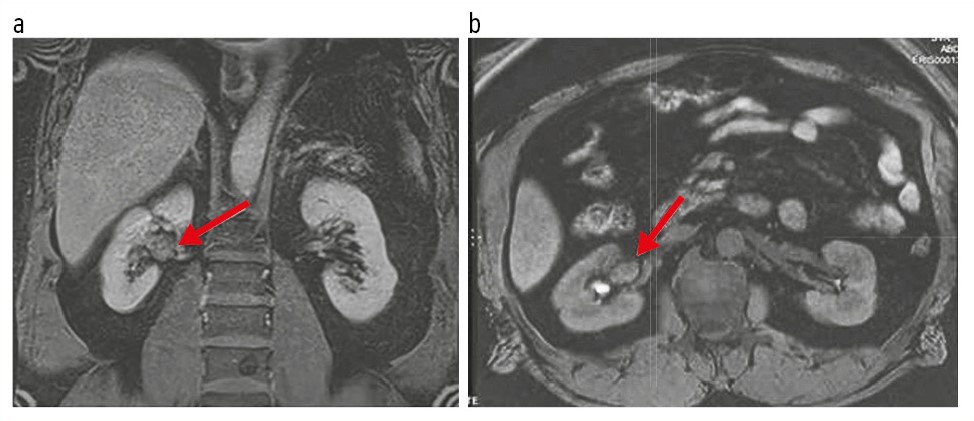

У пациента 56 лет при диспансерном обследовании с помощью ультразвукового исследования (УЗИ) почек выявлено образование в области почечного синуса справа размерами 29×15×20 мм с признаками васкуляризации. Какие-либо клинические проявления у больного отсутствовали. По данным мультиспиральной КТ брюшной полости и забрюшинного пространства с внутривенным контрастированием надпочечники с обеих сторон – без признаков узелков и гиперплазии. В воротах правой почки определяется мягкотканное образование, неоднородное по структуре, размером 29×15×20 мм. Плотность опухоли по шкале Хаунсфилда со средними значениями в нативе составляет +15 HU. Контрастный препарат накапливает неоднородно до +75 HU. Опухоль интимно прилежит к ветвям почечной артерии и вены (рис. 1).

Рис. 1. Пациент Г., 56 лет. Мультиспиральная КТ органов брюшной полости и забрюшинного пространства с контрастированием. На корональной (a), сагиттальной (b) и аксиальной (c) постконтрастных томограммах в синусе правой почки определяется овоидное образование неоднородной плотности, неоднородно накапливающее контраст.